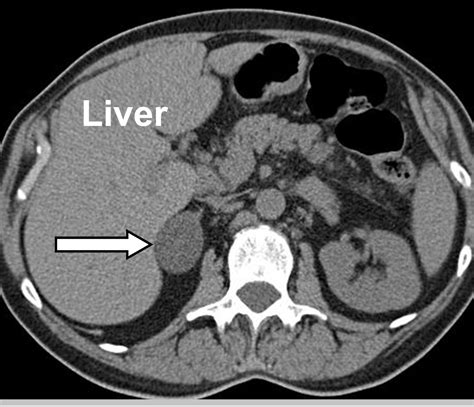

• Imaging Tests: Computed tomography (CT) scans and magnetic resonance imaging (MRI) are commonly used to visualize the adrenal glands and detect tumors. These tests can provide detailed images of the adrenal glands and help determine the size and characteristics of the tumor.